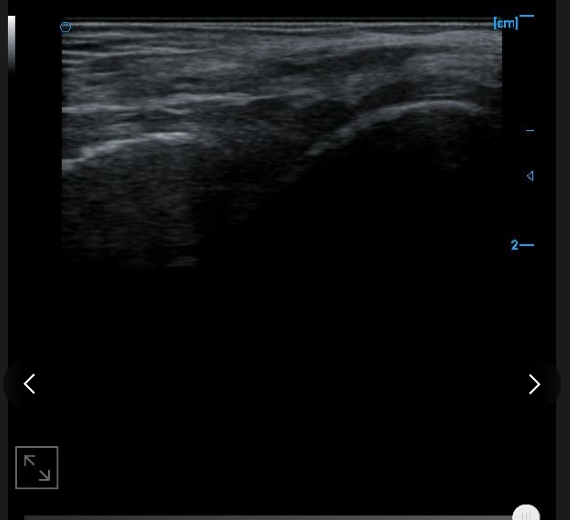

B-image of femoral trochlear cartilage